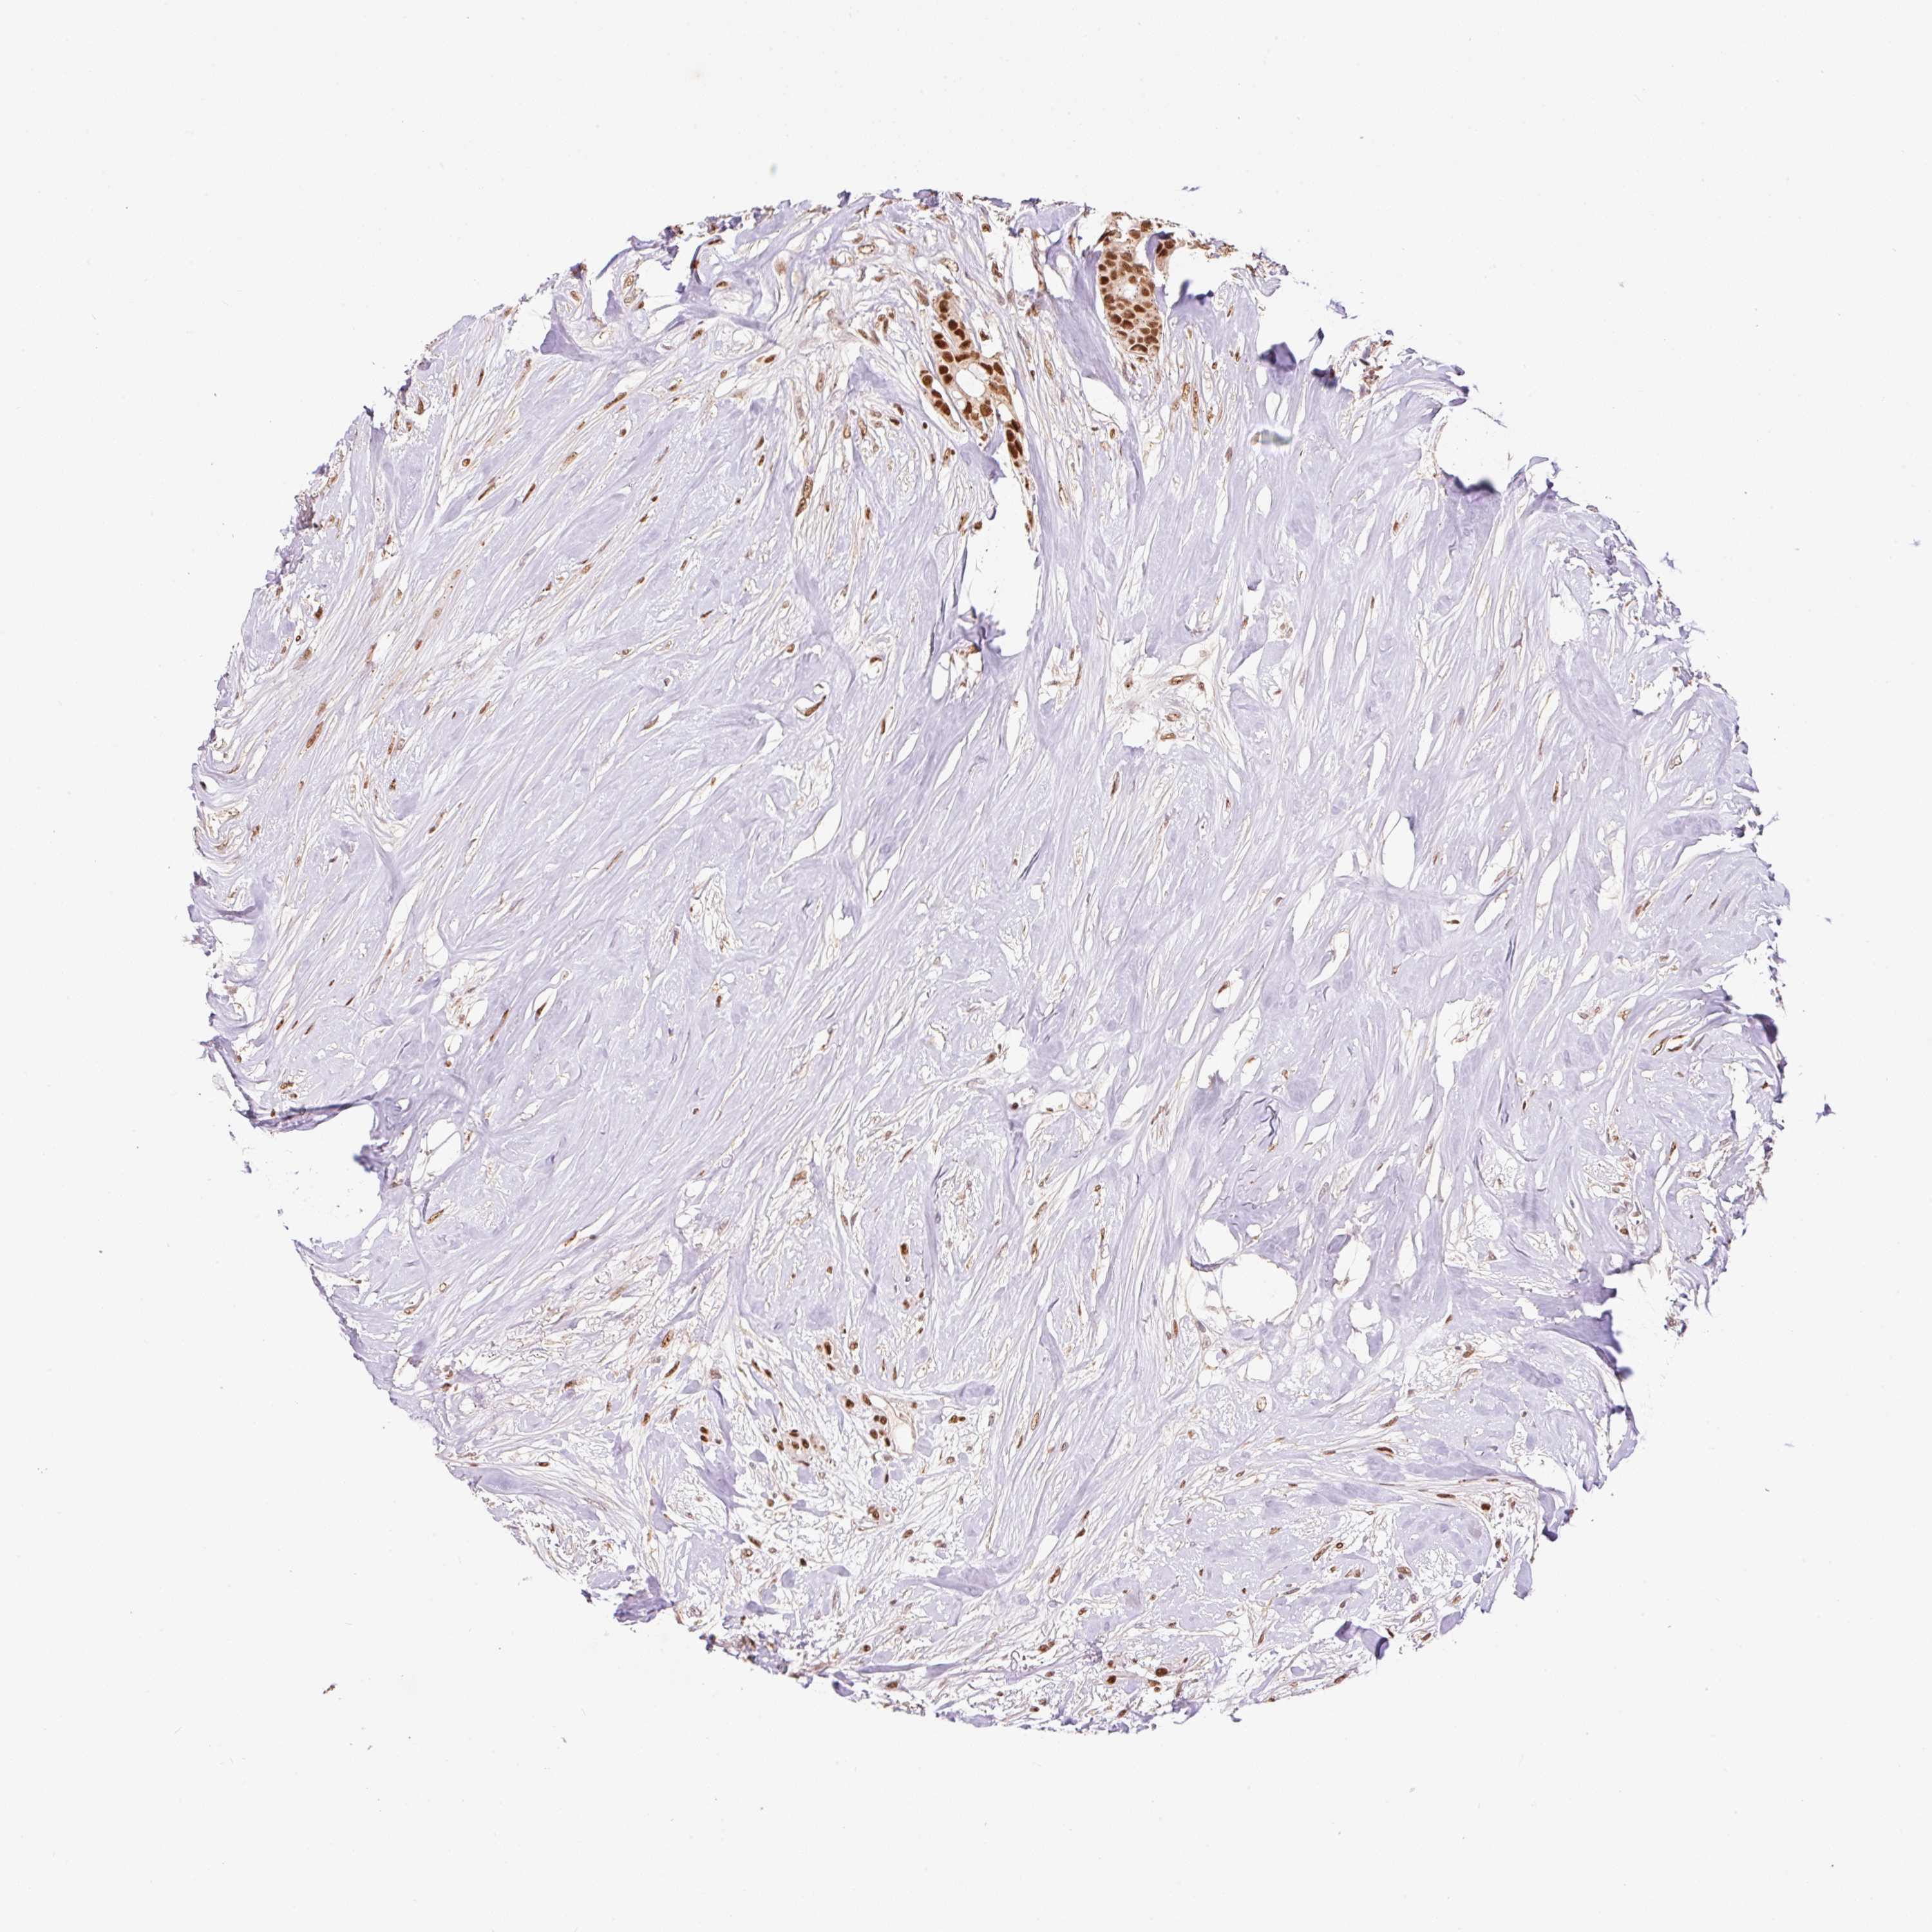

BRCA TCGA BRCA VALIDATION PROTEIN EXPRESSION

ANTIBODIES

AND

VALIDATION